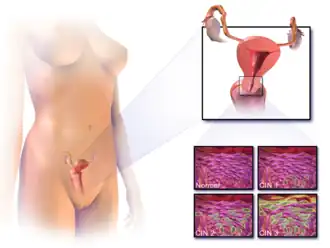

Câncer cervical

| Cancro do colo do útero | |

| Localização do cancro do colo do útero e exemplo de células normais e anormais | |

Cancro do colo do útero, cancro cervical (português europeu) ou câncer do colo de útero (português brasileiro) é o cancro que tem origem no colo do útero, ou cérvix.[1] Caracteriza-se pelo crescimento anormal de células que têm a capacidade de invadir ou de se espalhar para outras partes do corpo.[11] Na fase inicial geralmente não se observam sintomas. À medida que a doença avança podem-se manifestar sintomas como hemorragia vaginal, dores na pelve ou dores durante o ato sexual.[1] Embora a hemorragia após o ato sexual possa não ser grave, pode também ser um indicador da presença de cancro do colo do útero.[12]

Em mais de 90% dos casos da doença, a causa aparenta ser a infeção pelo vírus do papiloma humano (VPH ou HPV, do inglês human papiloma virus).[4][5] No entanto, a maioria das pessoas que é infetada pelo vírus não desenvolve cancro.[2][13] Entre outros fatores de risco estão o tabagismo, um sistema imunitário comprometido, a pílula contracetiva, a iniciação sexual precoce e múltiplos parceiros sexuais, embora estes fatores sejam menos relevantes.[1][3] O cancro do colo do útero geralmente desenvolve-se a partir de alterações pré-malignas que ocorrem ao longo de 10–20 anos.[2][3] Cerca de 90% dos casos são carcinomas de células escamosas, 10% são adenocarcinomas e um pequeno número são de outros tipos.[3] O diagnóstico é feito pela observação do colo do útero, seguida de biópsia. Posteriormente é usada imagiologia médica para determinar se o cancro se espalhou ou não.[1]

Neoplasia intraepitelial cervical, uma lesão com potencial precursor do câncer do colo do útero, é diagnosticada com frequência na biópsia do colo, examinada por um patologista. A nomenclatura neoplasia intraepitelial cervical é utilizada para alterações displásicas pré-malignas.

O nome e a classificação histológica das lesões precursoras do carcinoma do colo do útero foram muito modificadas ao longo do século XX. A classificação da Organização Mundial da Saúde[36][37] era baseada na descrição das lesões, classificando-as em displasia leve, moderada e grave ou carcinoma in situ (CIS). O termo neoplasia intraepitelial cervical (NIC) foi desenvolvido para enfatizar a gama de anormalidades dessas lesões e para ajudar a padronizar o tratamento.[37] Classifica-se a displasia leve como NIC I, displasia moderada como NIC II e displasia grave e carcinoma in situ como NIC III. Mais recentemente, NIC II e NIC III foram combinadas em NIC II/III. Estes são os resultados que devem ser relatados pelo patologista que analisar a biópsia.